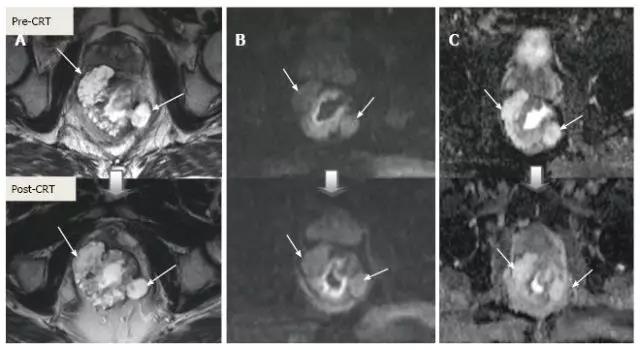

除了形态学发现之外,DWI 可以提供与细胞水平相关的功能信息变化。CRT 后细胞密度减低、纤维化或坏死使弥散加强,从而降低弥散加强图像的弥散信号强度,并增加在 ADC 图像 [ADC 值和 ADC 的信号强度(图 18 和图 19)。

虽然 DWI 能从纤维化中区分活的肿瘤细胞,也能区分治疗反应好与差,但不能预测完全缓解(图 20)。而且 CRT 后不能使用 DWI 评估肿瘤反应,因为即便在治疗前此类肿瘤也显示为 ADC 高密度(图 21)。

图 18. DWI 对放化疗后为 ypT3 的肿瘤重新分期。A. T2 加权轴位显示治疗后半圆形浸润肿瘤,与残留的 T3 肿瘤相符(箭头);B. 治疗后 DWI;C. ADC,图像分别对应肿瘤的高低信号强度,治疗前后 ADC 值分别为 0.68-0.72 和 1.22-1.44×10-3 mm²/s,治疗后 ADC 值增加与治疗反应相符。

图 19. DWI 对放化疗后 ypT0 直肠肿瘤重新分期。A. 治疗后 T2 加权轴位图像显示,先前直肠肿瘤区域的低信号强度纤维化厚壁(箭头),难以确定该区域是否含有肿瘤细胞还是完全缓解;B. 在治疗后 DW 图像(B-800)中,在以前的肿瘤区域(箭头)没有弥散信号,与完全缓解相符。在这种情况下,DWI 正确区分肿瘤与纤维化;C. ADC 图像显示治疗后平均 ADC 增加(0.70 × 10-3 mm²/s 对比 1.40 × 10-3 mm²/s)与治疗反应相符,但不能预测完全缓解。

图 20. DWI 对放化疗后 ypT0 直肠肿瘤重新分期。A. T2 加权轴位图像显示低信号强度纤维化的厚壁,可疑残留肿瘤区域具有中等信号强度(长箭头);B. 治疗后 DWI 图像,低信号强度的小焦点与残留肿瘤(长箭头)相符;C. ADC 图像显示治疗后平均 ADC 增加,与治疗反应相符, 但没有完全缓解。可疑直肠淋巴结(箭头)在 CRT 后 T2 和 DWI 不可见,但另外两个仍然可见(短箭头)。此例是 DWI 评估肿瘤和淋巴结反应假阳性。

图 21:粘液腺癌。粘液性肿瘤在治疗前后 T2,弥散和 ADC 图像均显示出高信号,无论其治疗反应如何。他们对 CRT 的反应不能使用 DWI 进行评估。